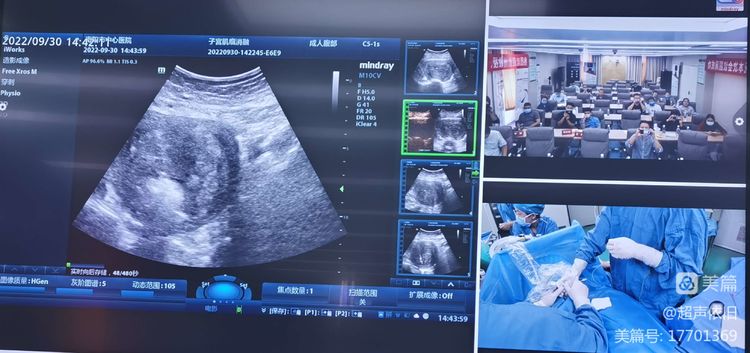

本次会议邀请到了知名介入超声专家郑州大学一附院董刚教授、河南省肿瘤医院李潜教授莅临授课,他们就“超声引导下妇科肿瘤消融”、“介入超声诊疗规范及注意事项”作了精彩的学术讲座;我院超声医学科门永忠主任、科室介入超声青年骨干郑章增主治医师、郭启龙主治医师分别就“超声引导下置管引流在临床急重症中的应用”、“超声引导下甲状腺结节消融”“超声引导下肝脏肿瘤消融”等进行了分享。市第一人民医院周锋主任、医专一附院刘玉森主任、镇平县人民医院李伟副院长、我院内分泌二病区徐娜主任、肝脏外科刘驰主任分别进行主持和精彩点评。下午进行了介入超声手术演示转播,病例包括子宫肌瘤消融、胆囊置管引流、肾囊肿硬化治疗、多部位组织活检等。参会人员除超声医学专业人员外,还有普外科、肿瘤内科、内分泌科等多学科同仁参加,会议取得圆满成功。

手术转播